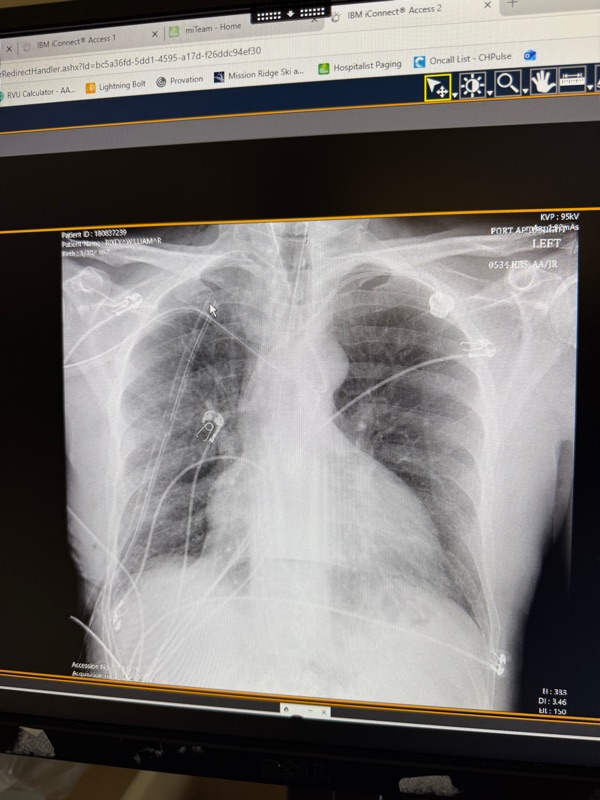

The photo above shows many of the things going into his body right now.

When Dr Loewen was in here this morning, I asked to see yesterday’s x-ray (thanks Debbie for recommending that I ask). It was so cool and here’s a pic of it above 🤞🏻. Check out all the tubes running around in his chest area. No wonder it hurts. That circle in upper right is his port-a-cath. They have told us they will access it today so that they can do blood 🩸 draws from his port instead of sticking him 💉each time, which is every day.